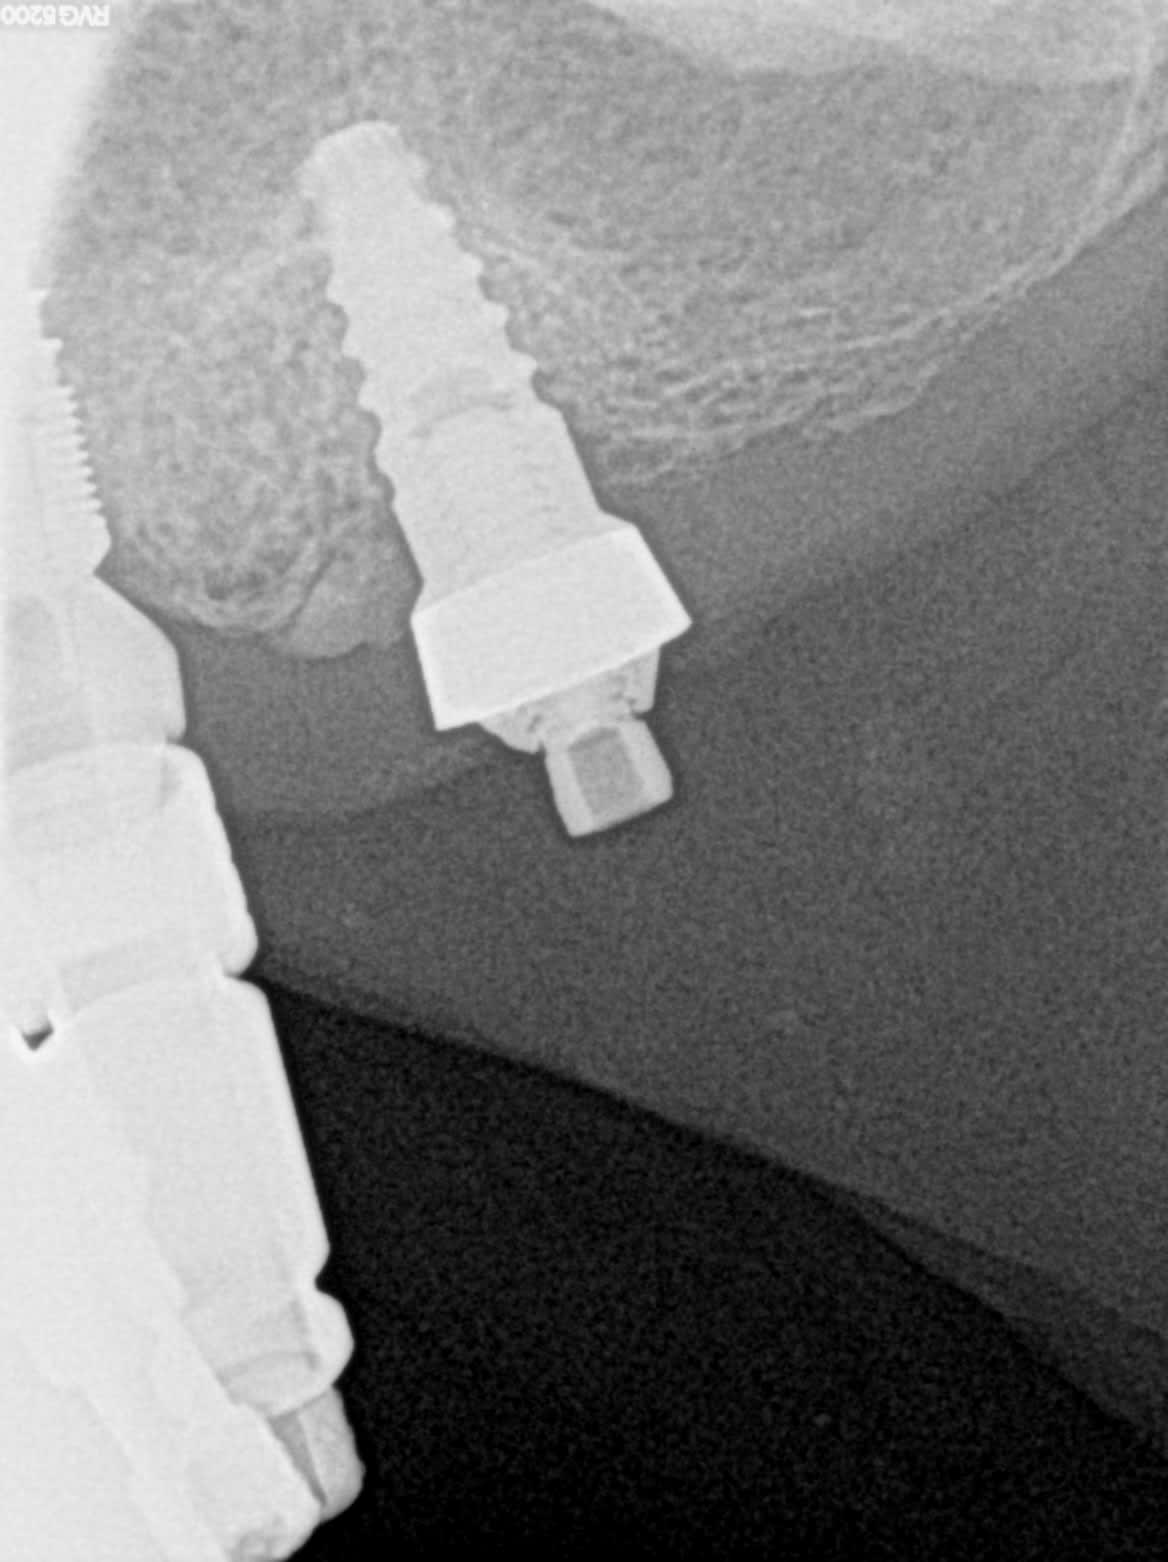

je dois refaire un all on 6 .

les 5 autres implants sont des ETK mais le patient est incapable de me donner la marque de celui-ci et aucun de mes tournevis n'est opérant .

une radio avec un contraste plus équilibré qu'on puisse avoir une idée de la connexion?

parce là.....

j'ai essayé d'améliorer le contraste , mais ce n'est pas beaucoup mieux .

si je pouvais dévisser le MUA , ce serait mieux mais je ne peux pas en l'état

Recherche terminée.

C'est un TBR Z1

je n'ai plus qu'à contacter la société TBR qui heureusement est à Toulouse . J'aurai l'accastillage rapidement. Enfin j'espère.